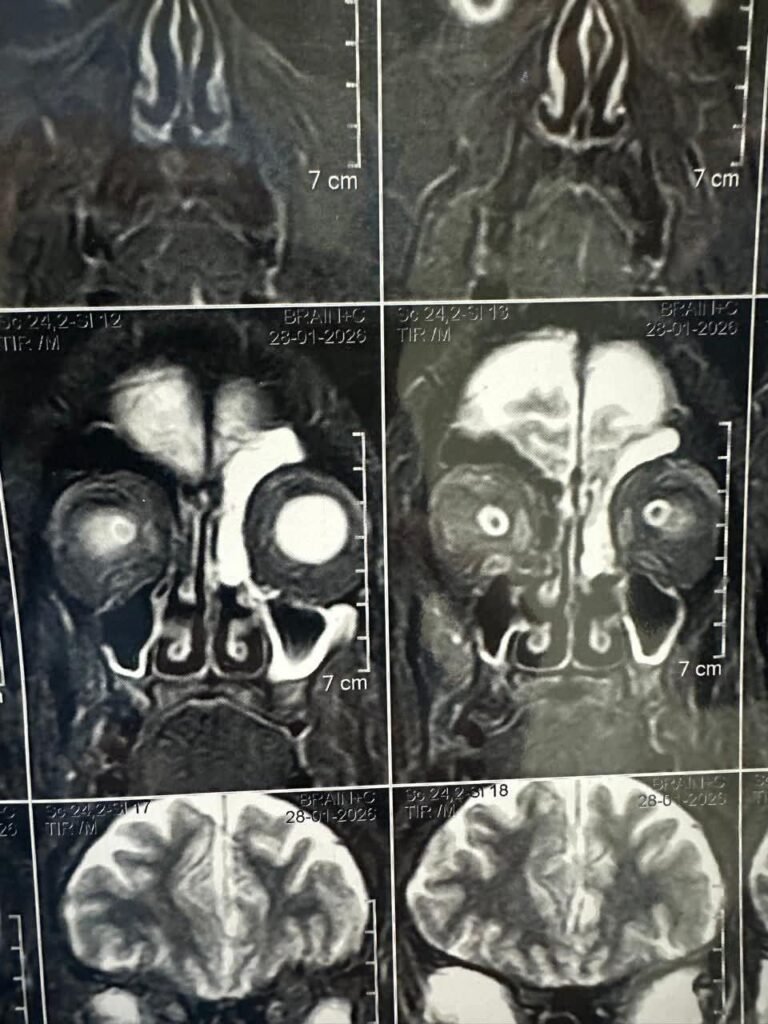

في إنجاز طبي جديد يُضاف إلى سجل النجاحات، نجح فريق قسم جراحة الأنف والأذن والحنجرة بـ مستشفى جامعة الأزهر في إجراء جراحة دقيقة لإصلاح ثقب بقاع الجمجمة الأمامي تسبب في تسرب بالسائل النخاعي عبر الأنف، وهي حالة خطيرة قد تؤدي إلى التهابات سحائية متكررة إذا لم يتم التعامل معها بصورة عاجلة ودقيقة.

وقد تم إصلاح الثقب باستخدام جراحة المناظير الأنفية الحديثة، مع غلق موضع التسرب بتقنية جراحية متقدمة تضمن إحكام الغلق وتقليل احتمالية عودة التسرب.